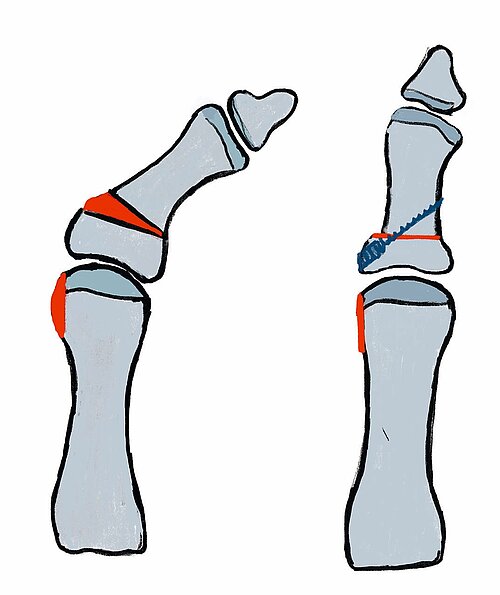

Definition: Korrektur einer Fehlstellung des Basisgliedes der Großzehe eine sog. Hallux valgus interphalangeus-Fehlstellung oft mit Tangieren der Zehenbeere D2.

Indikation: Fehlstellung mit Tangieren des Zehenmittel/-endgliedes der Zehe D2. OP-Methode der Wahl ist hier die Akin-Osteotomie.

OP-Technik (Abb. 4): Nach Abtragung der Pseudoexostose am Großzehenballen erfolgt eine keilförmige Osteotomie mit einem nach medial offenem Keil an der Basis der Grundphalanx der Großzehe im Sinne einer „close wedge“-Osteotomie. Die Fixation dieser Osteotomie, die nach dem Zuggurtungsprinzip durchgeführt wird, erfolgt meist mittels Spickdraht, Schraube oder spezieller Klammern [7].